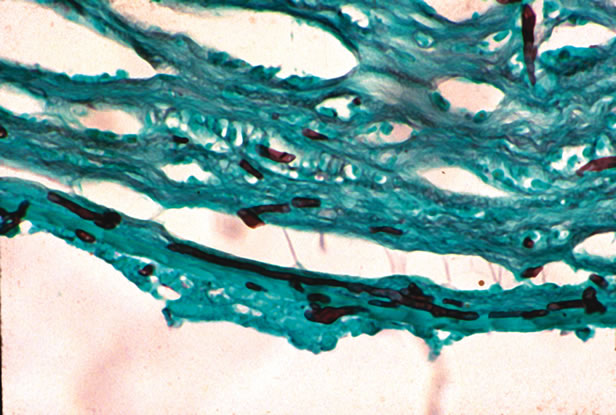

The most rapid technique for visualizing yeast or filamentous fungi is the potassium hydroxide (KOH) preparation. The scraping or swab is treated with 10% KOH in dimethyl sulfoxide. The strong base dissolves keratinized tissue (such as cornea), but the cell walls of fungi are resistant to dissolution. Both budding yeast and filamentous fungi can be visualized. Other staining methods also have high sensitivity for detection of yeast and fungi, including Giemsa stain, Gomori's methenamine silver (GMS), India ink staining, or periodic acid–Schiff (PAS) stain (Fig. 2). Fungi can also be identified on some Gram-stained samples.

Fig. 2. Fungal keratitis with branching septate hyphae, stained with Gomori's methenamine silver. (Photomicrograph courtesy of Dr. Morton Smith.)